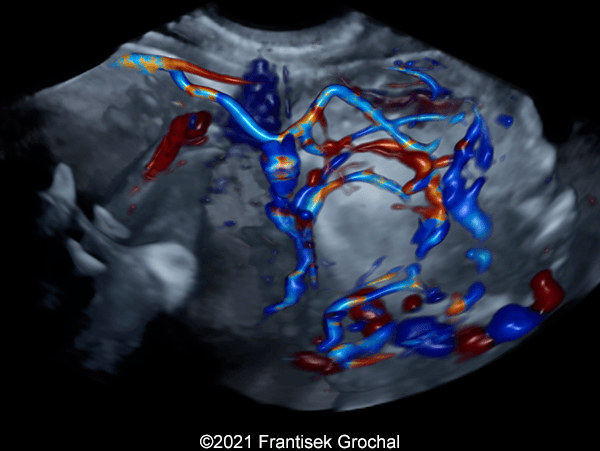

Case Report: A 24-year-old secundigravida, primipara presented to our office at 24 weeks and 6 days of her pregnancy due to a right-sided cranial parieto-occipital mass of the fetus. We obtained the following images.

We present a case of hemangioma-hemangioendothelioma.

Our ultrasound images at 24 weeks, 6 days show a highly vascularized, mostly solid mass measuring 58 x 45 x 34mm in the right-parieto-occipital subcutaneous region. Vascular supply of the lesion could be traced to the right vertebral artery. Repeat ultrasound exams done later in pregnancy demonstrated that the size of the mass remained stable with overall mass volume about 58 cm³.